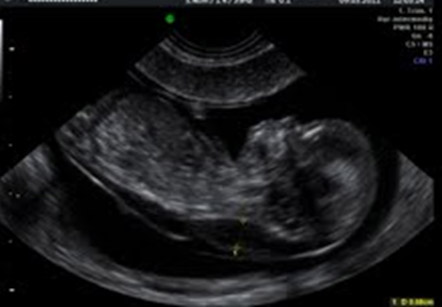

Translucencia nucal (TN) aumentada

Es un marcador tanto de cromosomopatías (síndrome de Down y otros) como de afectación cardiaca.